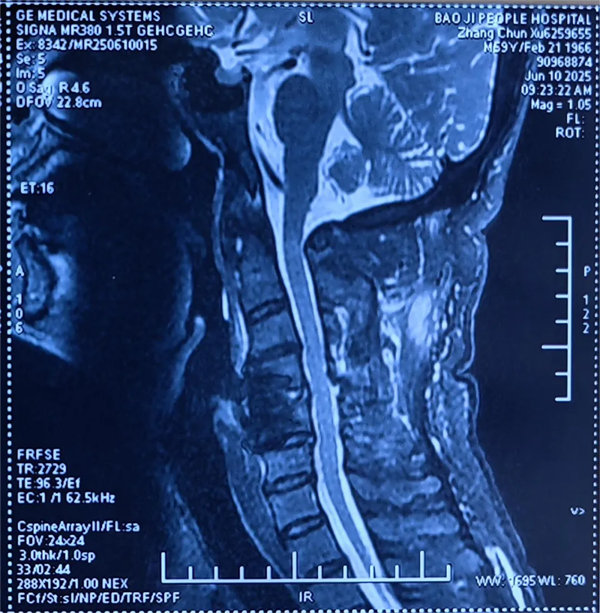

患者受傷后曾在外院接受保守治療,但肢體麻木癥狀持續(xù)存在。轉(zhuǎn)入我院時,頸椎CT及MRI顯示:頸4/5椎骨折脫位,脊髓受壓明顯,若不手術(shù)治療,可能面臨永久性神經(jīng)功能障礙。我院骨四科團(tuán)隊(duì),制定了前路ACDF手術(shù)方案:通過頸前側(cè)入路,切開復(fù)位、切除椎間盤,解除脊髓壓迫,同時植入融合器、鈦板固定,重建頸椎正常序列及穩(wěn)定性。術(shù)后患者麻木感消失,復(fù)查顯示頸椎序列恢復(fù)良好,目前已康復(fù)出院。

術(shù)后